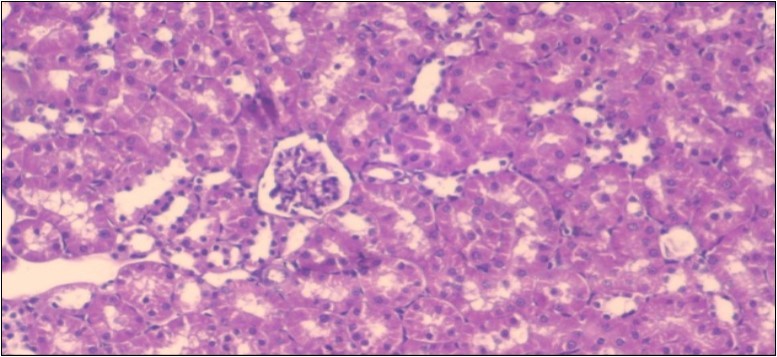

The histological examination of the kidney of the control rats fed on a standard diet showing normal rounded capsules with normal Bowman's glomeruli, round proximal tubules and elongated distal tubules with high cuboidal cells figure 1. The rats fed (HFD) showed fatty degeneration of the tubules with eosinophilic material deposition, glomerular atrophy with wide urinary space and distal tubules with extrusion of nuclei into lumen figure 2. By comparison kidneys of rats which were treated by fennel after being obese and the control rats observed partial improvement in both Bowman's capsules and proximal tubules. Note the distal tubules show less focal fatty infiltration figure 3.While examination of rats kidney that were treated by ator after obesity showed improvement in Bowman's capsules with normal glomerular and partial improvement in proximal tubules and distal tubules, figure 4. Kidney of rats that were treated by fennel and ator after obesity and the control rats showed high improvement in the tissues with normal glomerular and that Most of Bowman's capsules and renal tubules, restoring their normal appearance figure 5.

Figure 5.Photomicrograph of kidney section of treated rat with both fennel herb and Ator drug showing highly improved tissue with normal glomerular. Note, most Bowman's capsules and renal tubules, restoring their normal appearance (star). (H&E) (40X).

Photomicrograph of kidney section of treated rat with both fennel herb and Ator drug showing highly improved tissue with normal glomerular. Note, most Bowman's capsules and renal tubules, restoring their normal appearance (star).  (H&E) (40X).